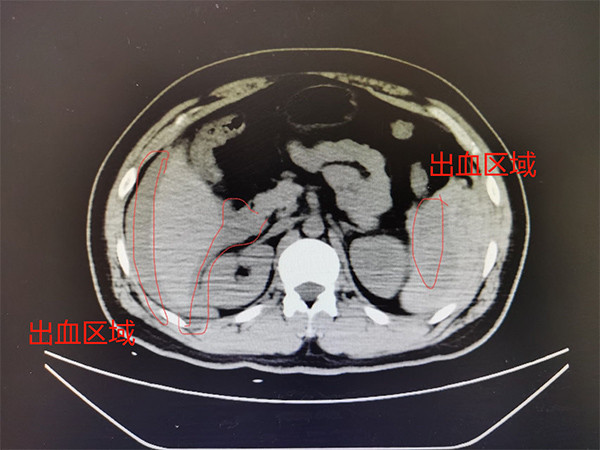

脾脏破裂伴积血影像表现分享,典型病例,过目不忘!

脾脏创伤性破裂一例